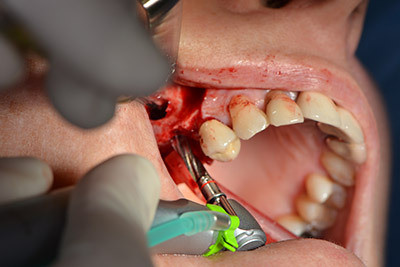

Die anschließenden Bohrungen werden mit einer reduzierten Umdrehungszahl von 300/min durchgeführt. Hier zeigt sich einer der Vorteile der Implantmed. Das chirurgische Protokoll kann voreingestellt werden – die einzelnen Positionen sind über einen einfachen Druck auf die Position „P“ der Fußsteuerung anwählbar. (Abb. 10 bis 11)

Schräge Bohrung

Abb. 10: Schräge Bohrung nach dorso-kranial mit 300/min.